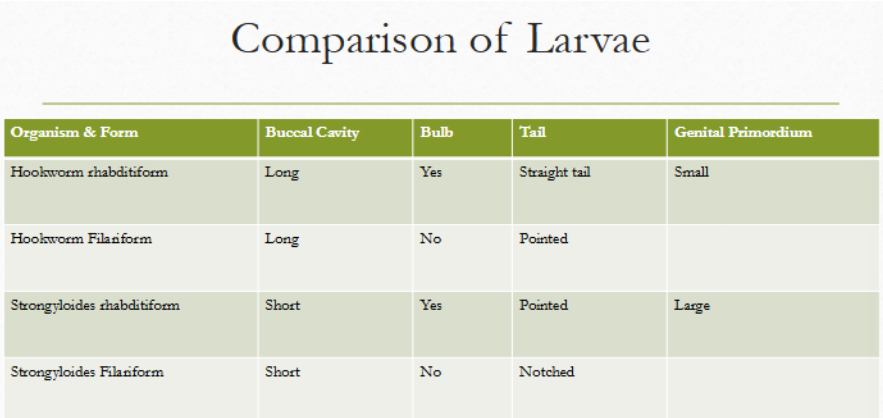

rhabditiform vs filariform

strongyloides stercoralis rhabditiform larvae

Short and sexy

first-stage larva as passed in the feces

esophagus is short (much less than 40% of the body) and distinctly bulbed, the short mouth capsule, and the large genital rudiment (GR)

the latter 2 characteristics distinguish these larvae from those of the hookworms

simple pointed tail

strongyloides stercoralis filariform larvae

esophagus extends to 40% of the body length

Focus carefully to notice the notched tail

Length of esophagus and the notch in the tail allow you to distinguish between the two larval forms

The esophagus does not have a bulb

hookworm rhabditiform larvae

Long buccal cavity

More than the width of the body

Genital primordium NOT visible

Esophagus is bulbed

strongyloides rhab vs filariform

rhabditiform: short buccal cavity; esophageal bulb; pointed tail; large genital primoridum

filariform: short buccal cavity; no esophageal bulb; notched tail

hookworm rhab vs filariform

rhabditiform: long buccal cavity; esophageal bulb; straight tail; small genital primordium

filariform: long buccal cavity; no esophageal bulb; pointed tail

strongyloides rhab vs hookworm rhab

strongyloides: short buccal cavity; esophageal bulb; pointed tail

hookworm: long buccal cavity; esophageal bulb; straight tail

strongyloides filariform vs hookworm filariform

strongyloides: short buccal cavity; no esophageal bulb; notched tail

hookworm: long buccal cavity; no esophageal bulb; pointed tail